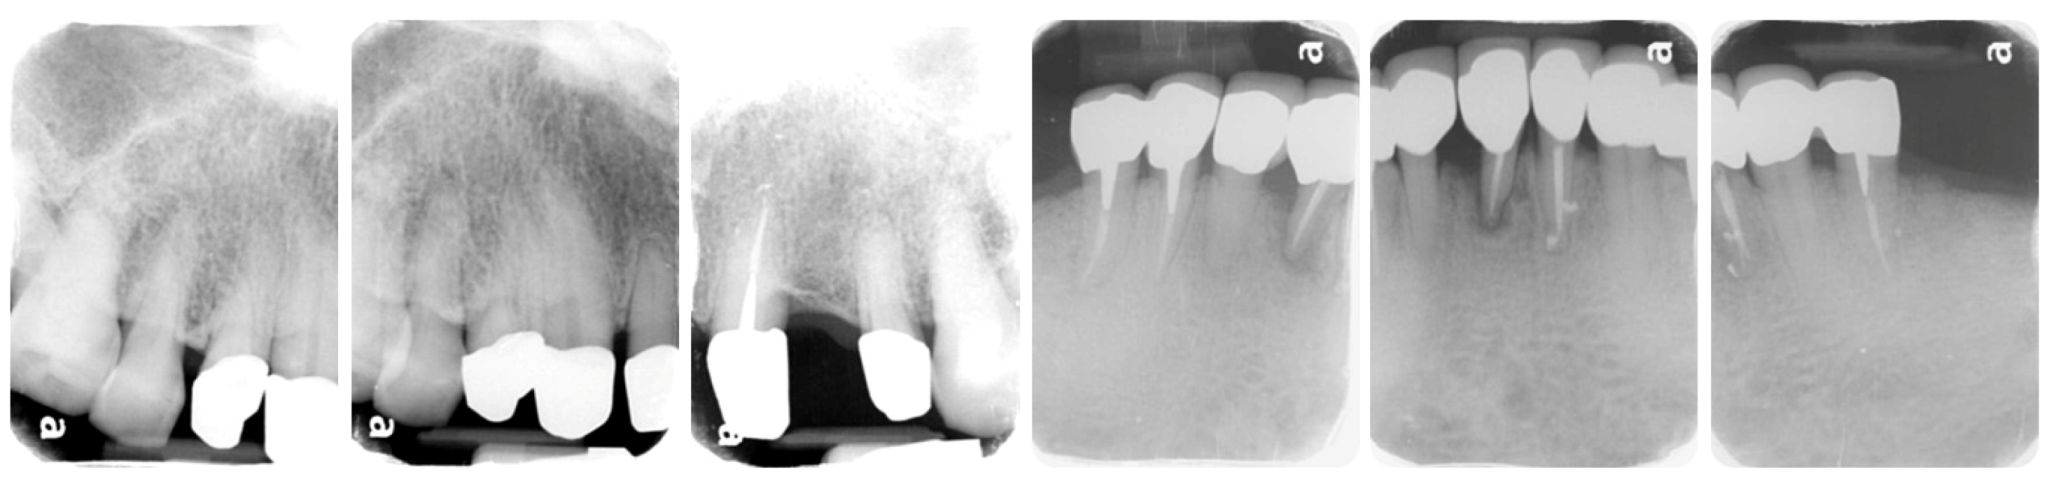

2. Case Description